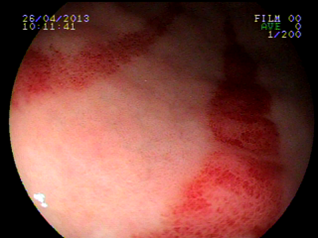

Ectasiva Vascular Antral